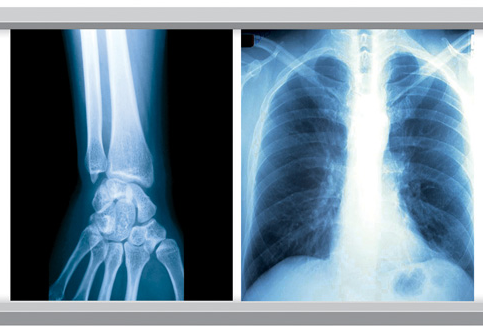

These dry films are designed especially for Dry Laser Images with blue color for the ultrasound Dept. and radiology Dept. of the hospital. This new film is laser processed and does not require wet processing chemistry, can accurately through the computer processing of all kinds of medical imaging, get rid of the traditional silver halide product show fixing bath processing program, and eliminate the flushing processing waste liquid pollution to the environment.

Sharp, clear images are assured by optimized control of image tones for CT, MRI, and other image modalities. Special new anti-halation technology increases image sharpness.

Blue White Base Medical X Ray Film 35x43CM 10x12 Inch X Ray Dry Film For Fuji Printer Images |